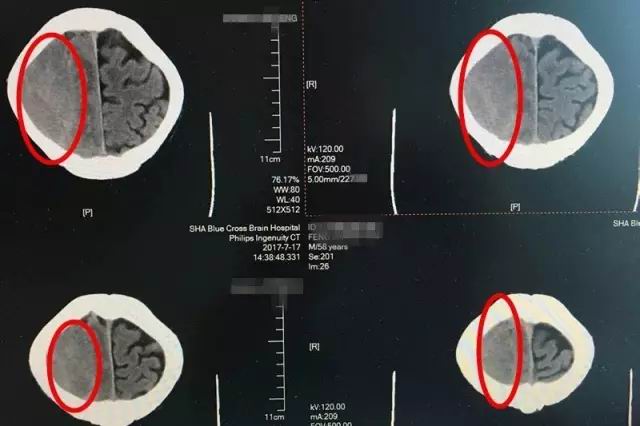

患者術(shù)前CT影像顯示:紅圈處為腦出血部位,出血量較大,顱內(nèi)壓升高

即便如此,時(shí)間不等人,等到七月中旬老馮一家輾轉(zhuǎn)打聽(tīng)到上海藍(lán)十字腦科醫(yī)院,慕名找到神經(jīng)內(nèi)科的李振并主任時(shí),老馮的癥狀已經(jīng)開(kāi)始加重了。入院時(shí)的腦CT影像檢查顯示,患者出血量增加,腦中線明顯移位變質(zhì),左側(cè)肢肌力3級(jí)(在和地心引力相反的方向中尚能完成其動(dòng)作,但不能對(duì)抗外加的阻力),而且,他開(kāi)始出現(xiàn)嗜睡、不思飲食的情況,如果再不及時(shí)治療,患者很可能會(huì)陷入昏迷、偏癱、失語(yǔ)、癲癇,巨大的風(fēng)險(xiǎn)正一步一步靠近。因此,迅速制定合理的治療方案,才能及時(shí)挽救患者。